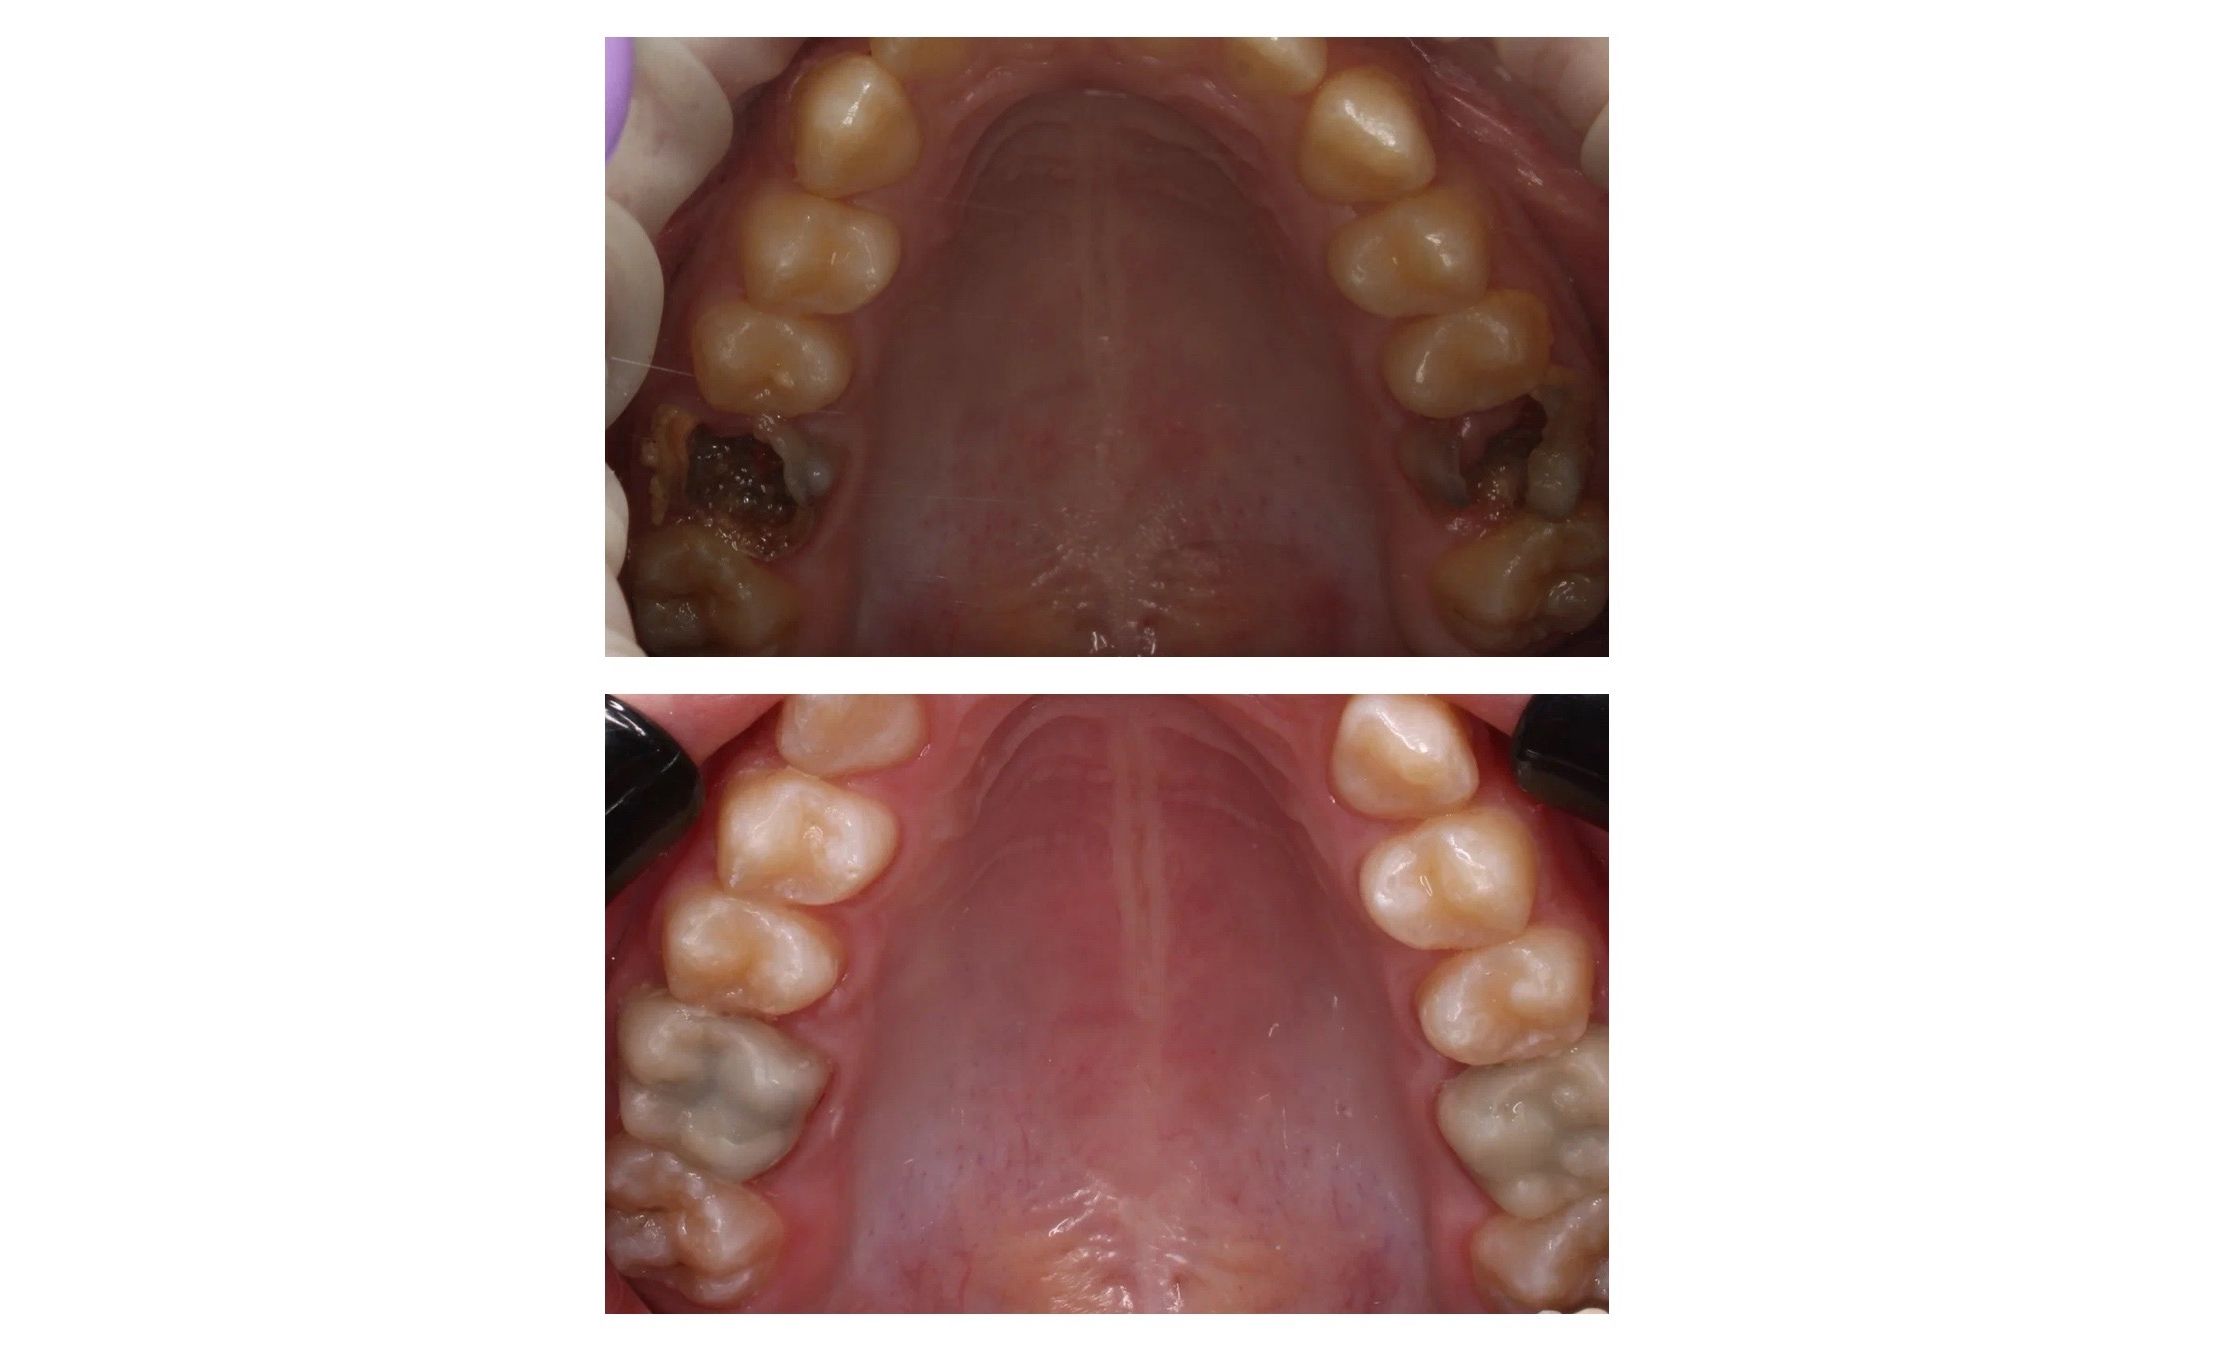

Эндодонтическое лечение с последующей временной ортопедической реабилитацией.

Рахмановой М. А., Бортникова Д.С.

Эндодонтическое лечение с последующей временной ортопедической реабилитацией